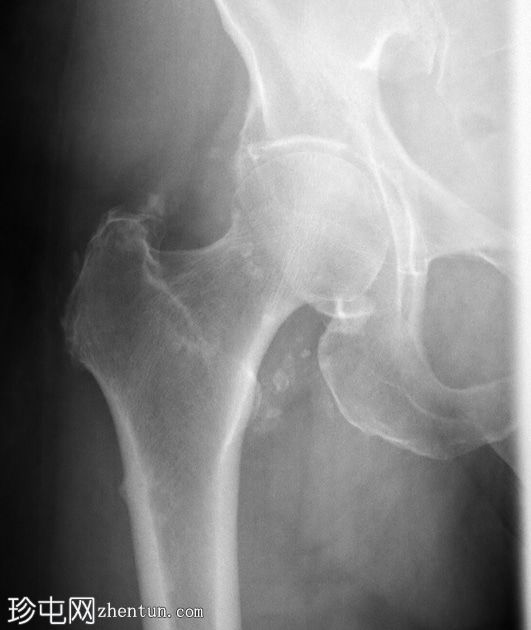

6.jpg

轴向PD

脂肪饱和度

一条水平T1和T2低信号骨折线横断右股骨干外侧皮质。近1/3的骨干周长受累,并伴有邻近骨髓水肿。其余皮质骨完整。左股骨未见异常。

该患者有长期服用双膦酸盐类药物的病史,这是众所周知的股骨功能不全性骨折的危险因素。不完全性骨折会影响股骨外侧皮质,如本例所示,应立即治疗,否则可能发展为完全性骨折。治疗方案包括立即停用双膦酸盐类药物并进行髓内钉固定。由于此类骨折通常是双侧的,因此应始终对对侧股骨进行影像学检查。